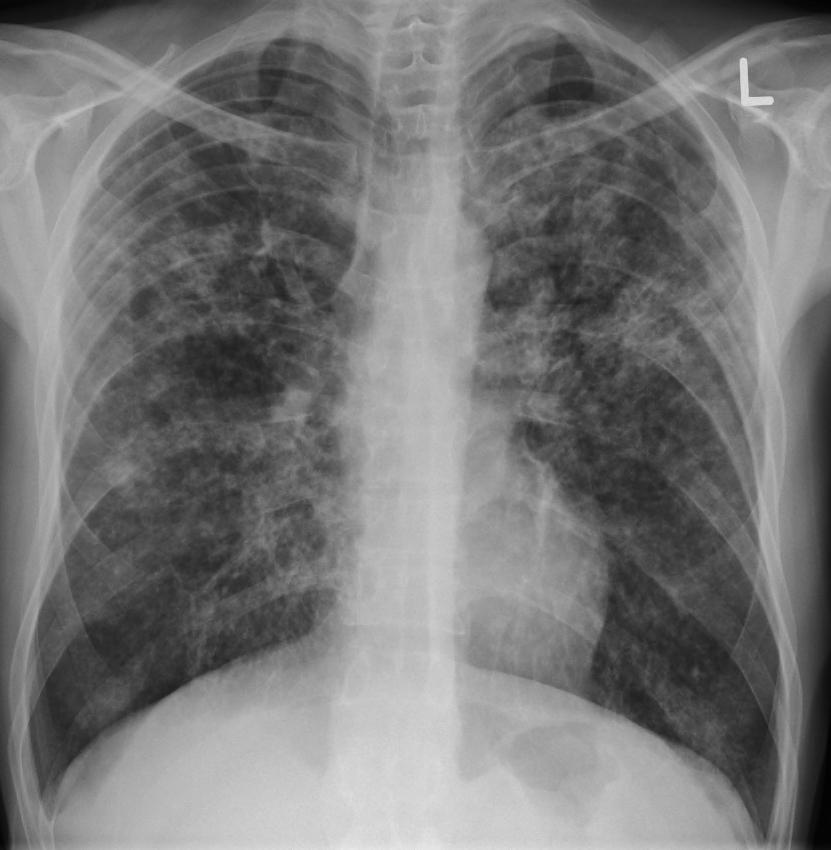

Микроскопическое исследование нативных и фиксированных окрашенных препаратов мокроты позволяет подробно изучить ее клеточный состав, и известной степени отражающий характер патологического процесса в легких и бронхах, его активность, выявить различные волокнистые и кристаллические образования, также имеющие важное диагностическое значение, и, наконец, ориентировочно оценить состояние микробной флоры дыхательных путей (бактериоскопия).

Из клеточных элементов, которые можно обнаружить в мокроте больных пневмонией, диагностическое значение имеют эпителиальные клетки, альвеолярные макрофаги, лейкоциты и эритроциты.

Эластические волокна. Следует упомянуть также еще об одном элементе мокроты пластических волокнах, которые появляются в мокроте при деструкции легочной ткани (абсцесс легкого, туберкулез, распадающийся рак легкого и др.). Эластические волокна представлены в мокроте в виде тонких двухконтурных, извитых нитей с дихотомическим делением на концах. Появление эластических волокон в мокроте у больных с тяжелым течением пневмонии свидетельствует о возникновении одного из осложнений заболевания — абсцедировании ткани легкого. В ряде случаев при формировании абсцесса легкого эластические волокна в мокроте можно обнаружить даже несколько раньше, чем соответствующие рентгенологические изменения.

Признаками активного воспалительного процесса в легких являются:

1. характер мокроты (слизисто-гнойная или гнойная);

2. увеличение количества нейтрофилов в мокроте, в том числе их дегенеративных форм;

3. увеличение количества альвеолярных макрофагов (от единичных скоплений из нескольких клеток в поле зрения и больше);

Появление в мокроте эластических волокон свидетельствует о деструкции легочной ткани и формировании абсцесса легкого.

Окончательные выводы о наличии и степени активности воспаления и деструкции легочной ткани формируются только при их сопоставлении с клинической картиной заболевания и результатами других лабораторных и инструментальных методов исследования.

Микроскопия мазков мокроты, окрашенных по Граму, и изучение микробной флоры (бактериоскопия) у части больных пневмонией позволяет ориентировочно установить наиболее вероятного возбудителя легочной инфекции. Этот простой метод экспресс-диагностики возбудителя недостаточно точен и должен использоваться только в комплексе с другими (микробиологическими, иммунологическими) методами исследования мокроты. Иммерсионная микроскопия окрашенных мазков мокроты иногда бывает весьма полезной для экстренного подбора и назначения адекватной антибактериальной терапии. Правда, следует иметь в виду возможность обсеменения бронхиального содержимого микрофлорой верхних дыхательных путей и ротовой полости, особенно при неправильном сборе мокроты.

При окраске по Граму в мазке мокроты иногда можно достаточно хорошо идентифицировать грамположительные пневмококки, стрептококки, стафилококки и группу грамотрицательных бактерий — клебсиеллу, палочку Пфейффера, кишечную палочку и др. При этом грамположительные бактерии приобретают синий цвет, а грамотрицательные — красный.

Предварительная бактериоскопия мокроты является наиболее простым способом верификации возбудителя пневмонии и имеет определенное значение для выбора оптимальной терапии антибиотиками. Например, при обнаружении в мазках, окрашенных по Грамму, громположительных диплококков (пневмококков) или стафилококков вместо антибиотиков широкого спектра действия, увеличивающих риск селекции и распространения аитибиотикорезистентных микроорганизмов, возможно назначение целенаправленной терапии, активной в отношении пневмококков или стафилококков. В других случаях выявление преобладающей в мазках грамотрицательной флоры может указывать па то, что возбудителем пневмонии являются грамотрицательные энтеробактерии (клебсиелла, кишечная палочка и т.п.), что требует назначения соответствующей целенаправленной терапии.